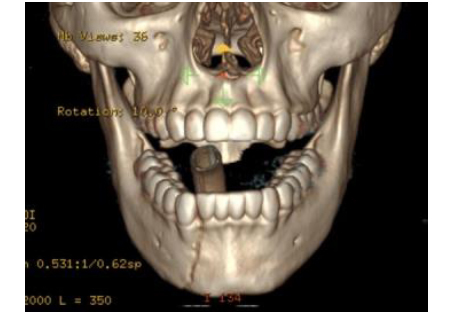

A 16-year-old girl is brought to the emergency department after sustaining fractures to the mandible in a rollover motor vehicle collision. She is intubated during the primary survey because of her critical airway. A CT scan is shown. Which of the following is the most appropriate treatment of this fracture pattern?

The correct response is Option C.

This CT scan shows right–body and left–angle fractures, both with clinically significant displacement. Modern facial fracture management dictates early primary reduction and repair; therefore observation and soft diet without surgery is incorrect, as is avoiding disturbance of the mandible and allowing 6 weeks of bone healing. Since she has reached the age of skeletal maturity permanent titanium hardware is an accepted modality of treatment; therefore it is incorrect to avoid hardware and rely on non-reduced maxillomandibular fixation. In addition, an angle fracture cannot typically be treated with maxillomandibular fixation alone, but requires a Champy plate or more rigid fixation. Open reduction and internal fixation of the right–body fracture, without repairing the left angle is incorrect, as Champy lines do not preclude the need for fixation. Open reduction and internal fixation of both the right body and the left angle fractures is correct, as both fractures need to be reduced, and then fixated, for the best chance of restoring occlusion.